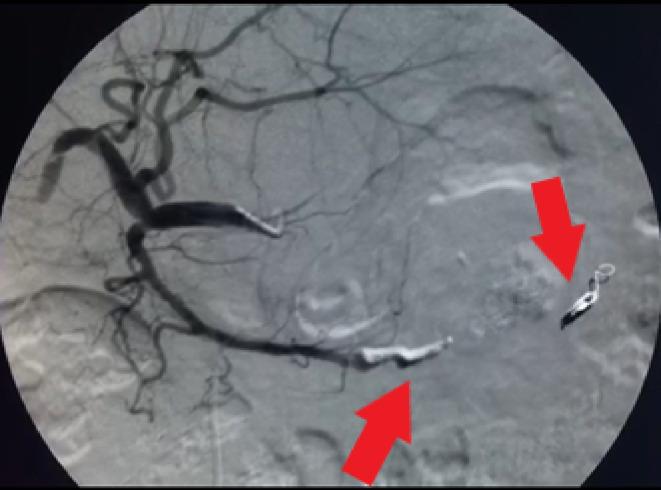

A 55-year-old woman with a history of coronary artery disease was referred to our hospital with abdominal pain as her primary complaint. Early works revealed anemia, a small amount of free peritoneal fluid, and a possible large aneurysm or pseudoaneurysm by the greater curvature of the stomach. She underwent emergency angiography that showed a large aneurism/pseudoaneurysm of the gastroepiploic artery. Successful embolization of the lesion was performed using the isolation technique. Perforation of a side branch of the gastroduodenal artery was observed on the immediate postembolization control angiography. Therefore, parent artery coiling was done immediately with good results. She was symptom-free and stable hemodynamically after the procedure, during the hospital course, and in the follow-ups.

一名有冠状动脉疾病史的55岁女性因腹痛为主诉被转诊至我院。早期检查发现贫血、少量腹腔游离液体,胃大弯处可能存在大动脉瘤或假性动脉瘤。她接受了急诊血管造影,显示胃网膜动脉有一个大动脉瘤/假性动脉瘤。采用隔离技术成功栓塞了该病变。栓塞后即刻控制血管造影观察到胃十二指肠动脉一分支穿孔。因此,立即对供血动脉进行了弹簧圈栓塞,效果良好。术后、住院期间及随访过程中她均无症状且血流动力学稳定。